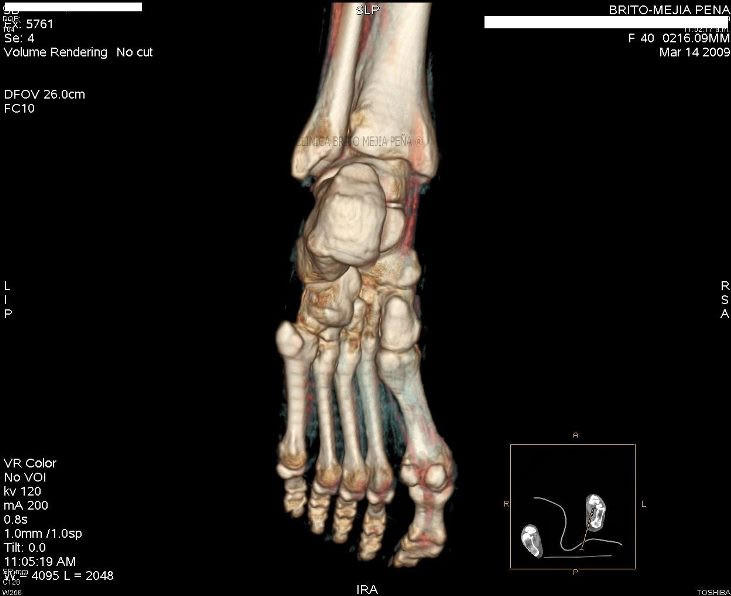

Pié normal posterior